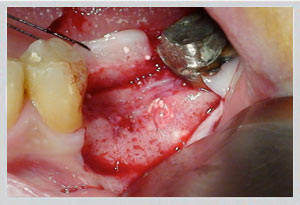

Upper jaw: GBR (guided bone regeneration) for moderate buccal defects; block bone grafting for larger volume requirements. Socket preservation at time of extraction prevents bone loss from occurring in the first place.

Lower jaw: Block bone grafting for severe buccal wall defects. Easy Graft Crystal (non-resorbable beta-tricalcium phosphate) for minor to moderate deficiencies. Socket preservation equally critical.

Dr. Zarifeh's preferred protocol combines synthetic Easy Graft with autogenous bone chips — pairing the structural scaffold of a synthetic material with the biological activity of the patient's own cells. The selection is made individually per case based on defect size, location, and planned implant timeline.